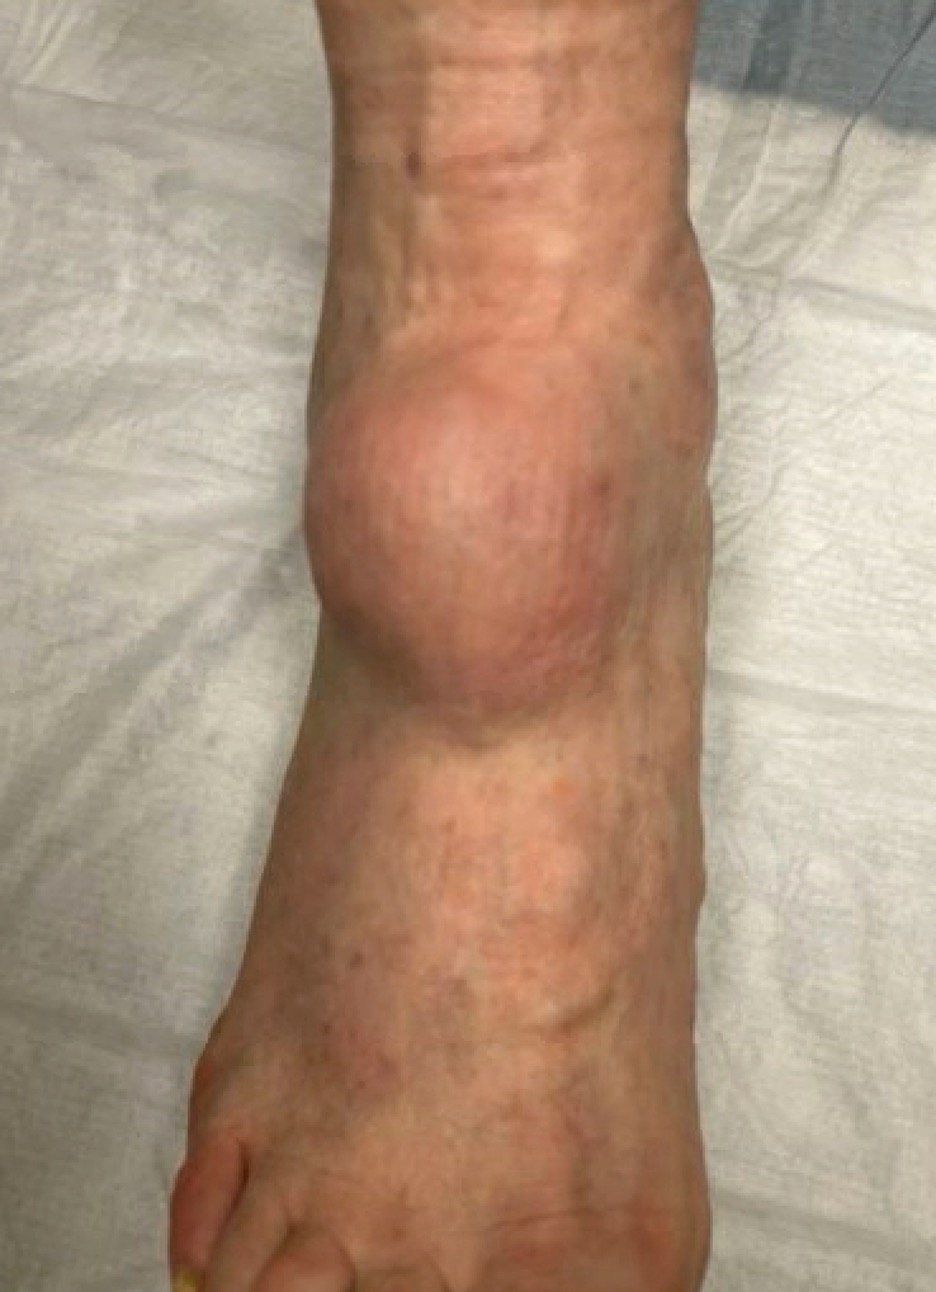

A 90-year-old male patient presented to our clinic with a chief complaint of a soft tissue mass at the right anterior ankle that had slowly increased in size over the past year. He denied pain to the lesion and denied neurological changes to the surrounding soft tissues. His past medical history was significant for lung cancer as well as basal cell carcinoma to the forearm. Physical exam revealed a 7 x 7 cm firm, well-adhered soft tissue mass protruding from the right anterior ankle (Figures 1-2).

On physical exam, he was neurovascularly intact. There was no tenderness to palpation of the mass, and ankle joint range of motion was unrestricted with full function and strength of the tibialis anterior and long extensor tendons. The patient only complained of difficulty donning shoe gear. Core biopsies of the mass, taken at an outside facility, revealed a predominantly fibrous, fibrillary hypocellular, low-grade spindle cell lesion with no signs of atypia or mitotic activity. Plain films revealed arterial calcifications but were unremarkable for any osseous erosions.